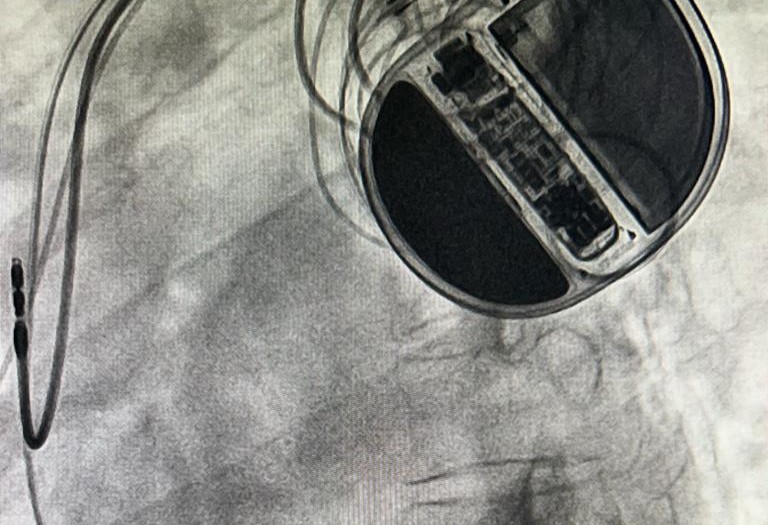

Naharlagun: In a historic first for Arunachal, a 29-year-old female diagnosed with Dilated Cardiomyopathy (DCMP), Severe Left Ventricular Dysfunction and complete left bundle branch block, unresponsive to optimal guideline-directed medical therapy, underwent a successful implantation of Cardiac Resynchronization Therapy with Defibrillator (CRT-D) at the cath lab of the department of cardiology at TRIHMS.

CRT-D is pivotal in restoring synchronization between the heart’s ventricles, a condition lost in certain subsets of patients with chronic heart failure, increasing susceptibility to heart failure-related complications.

The successful CRT-D implantation not only enhances the patient’s ejection fraction but also improves the quality of life and reduces mortality.

The integrated defibrillator component acts as a preventive measure against cardiac arrest.